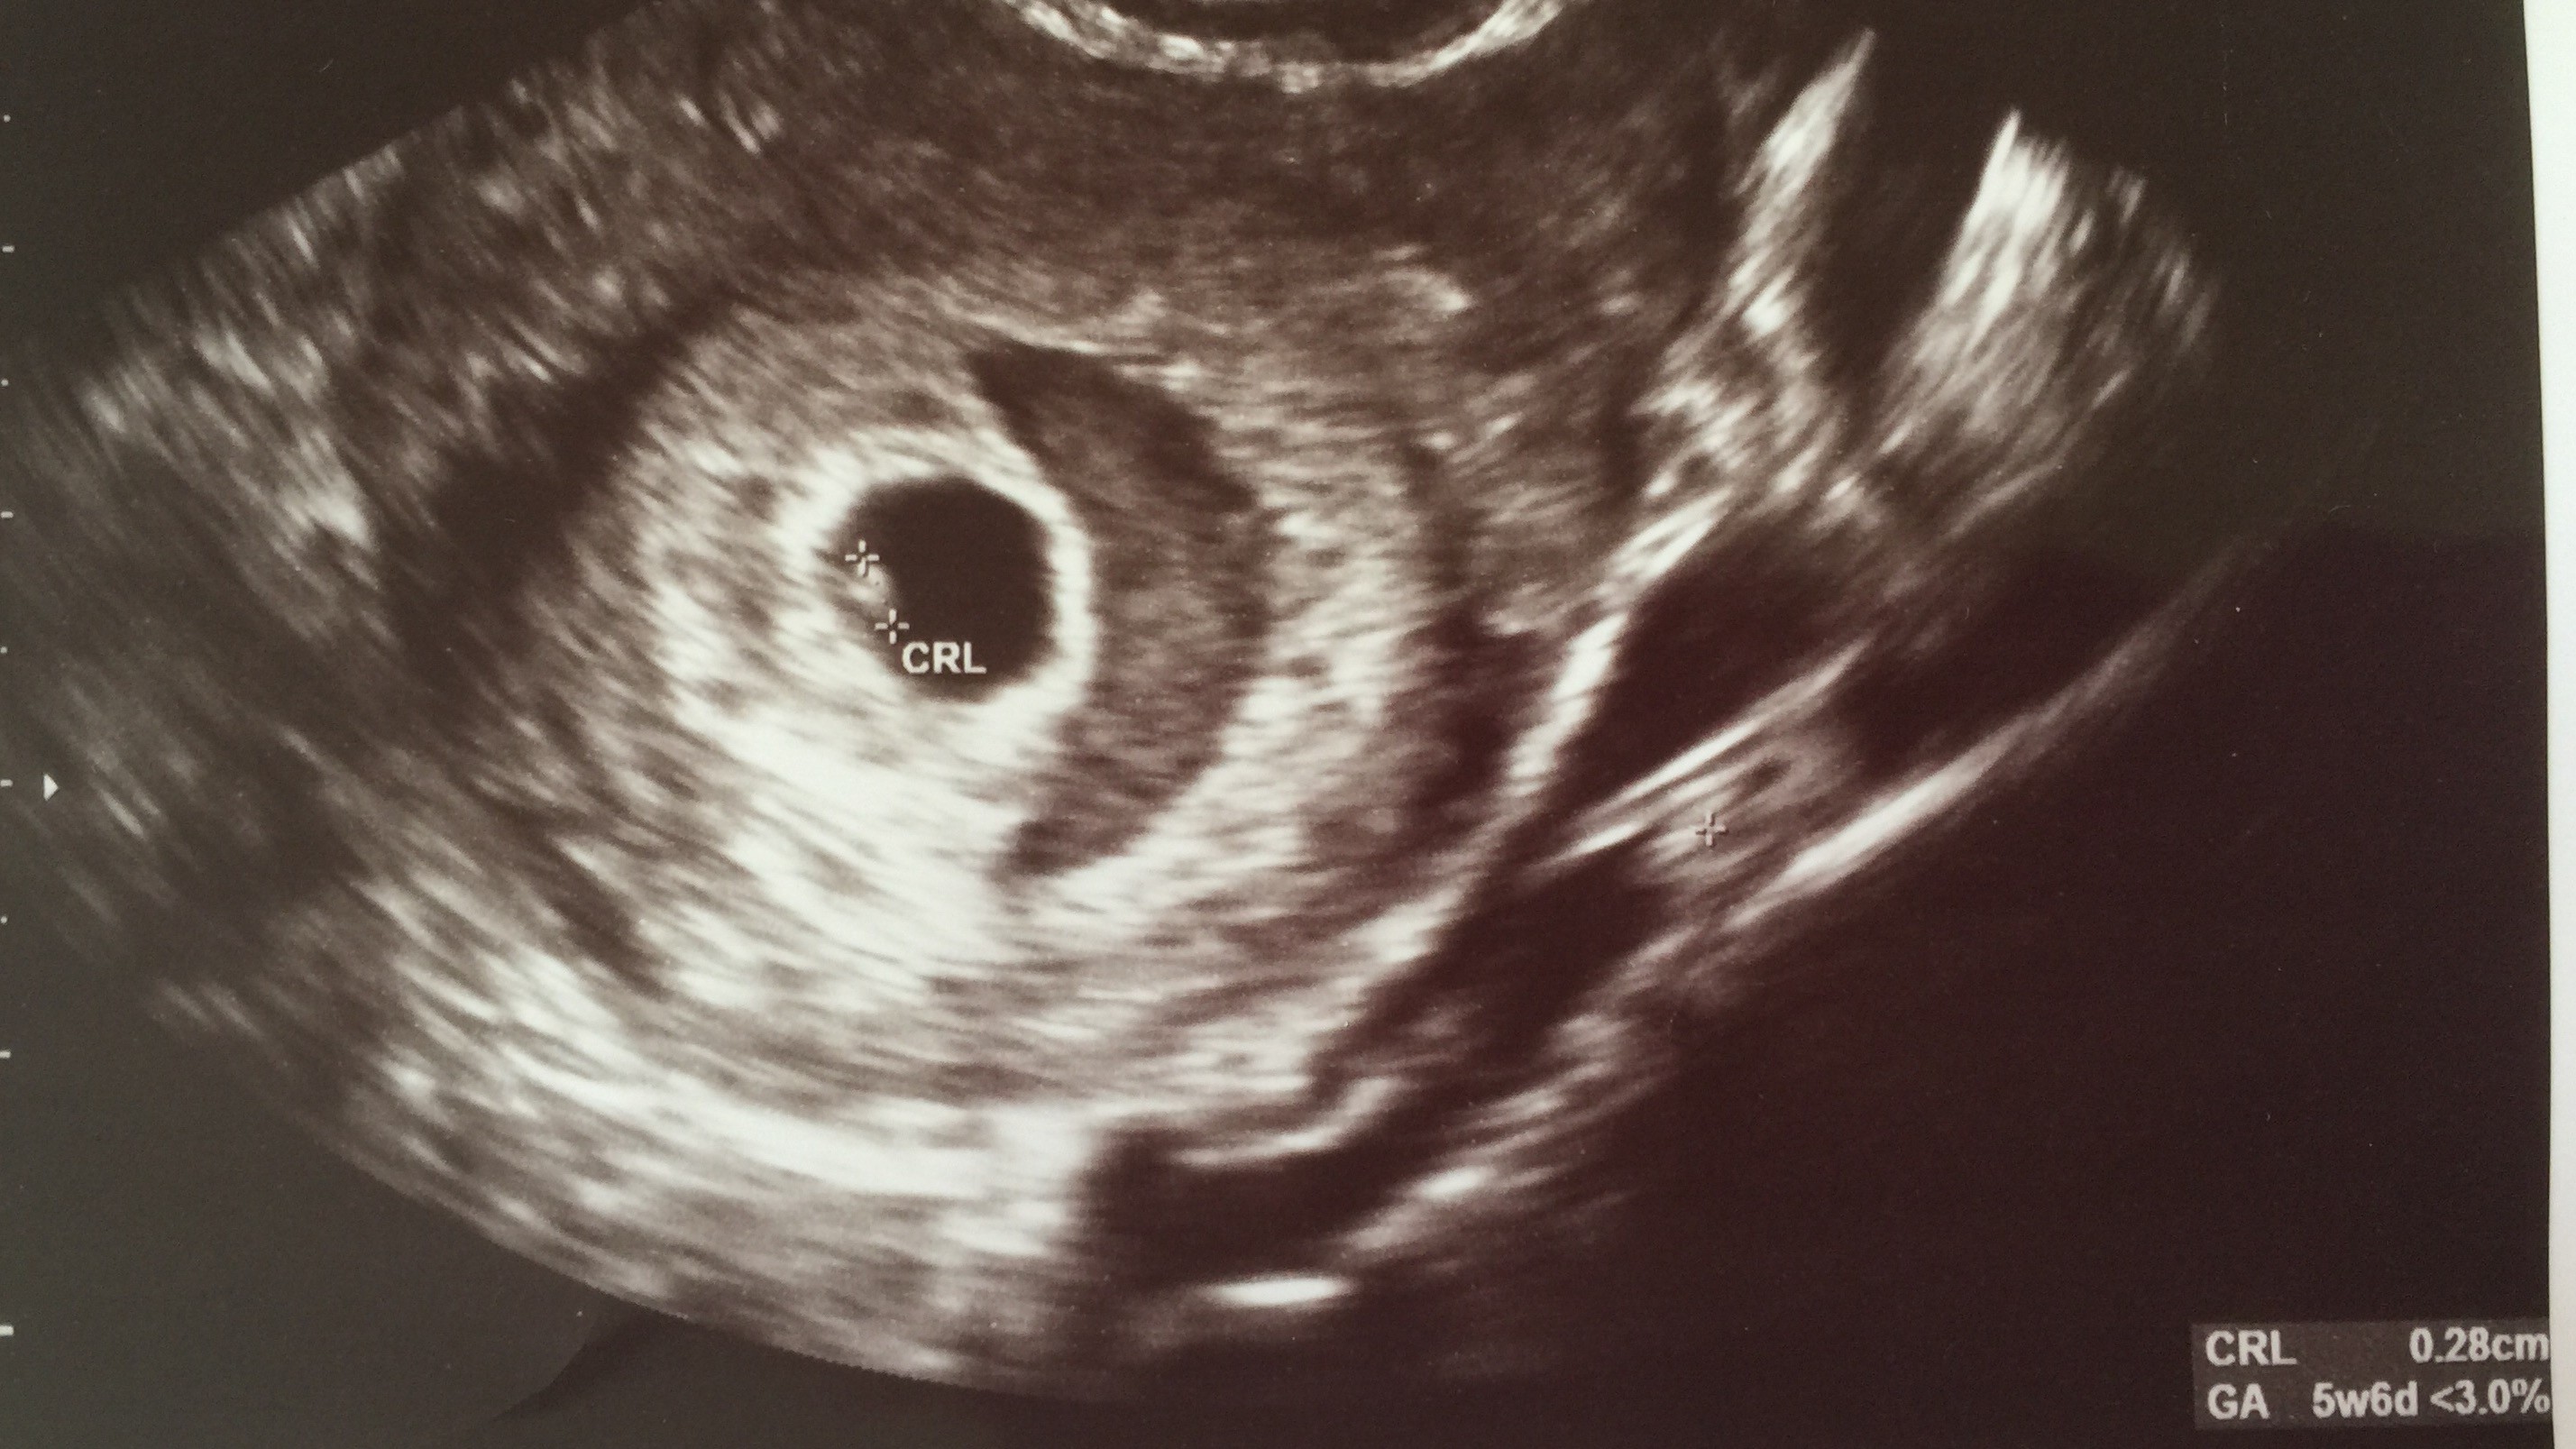

Ten półksiężyc to krwiak